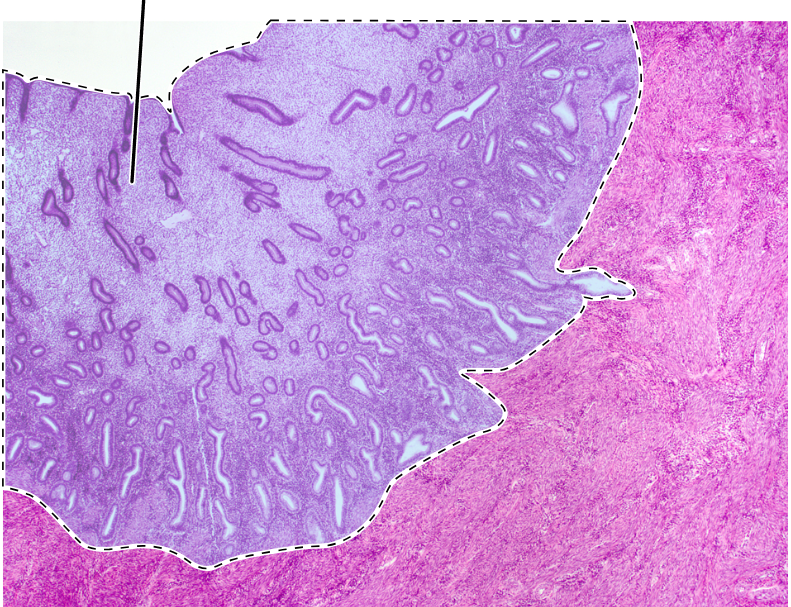

uterus

endometrium

uterine glands

myometrium